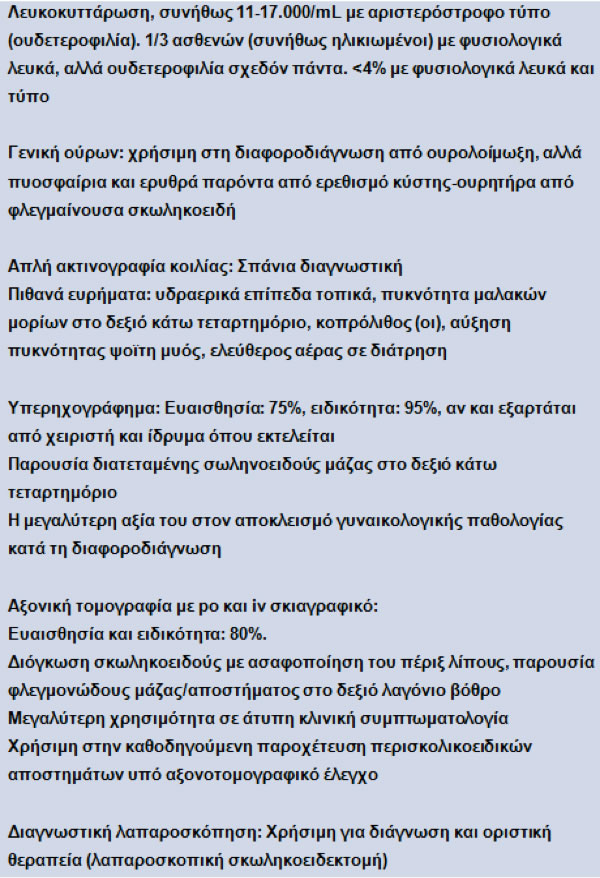

Παρακλινικός έλεγχος

Στον Πίνακα 4 συνοψίζονται τα εργαστηριακά και απεικονιστικά ευρήματα.

Πίνακας 4.

Ευρήματα από τον παρακλινικό έλεγχο σε οξεία σκωληκοειδίτιδα